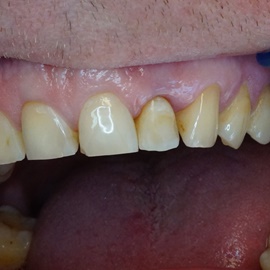

Wybielanie obejmujące pojedyncze zęby jest dość często spotykane. Najczęstszą przyczyną dyskoloracji zęba jest obumarcie miazgi i brak następowego poprawnego leczenia kanałowego, lub leczenie nieprawidłowe. Czasami udaje się przeprowadzić proces wybielania, który jest zadowalający dla pacjenta, a czasami w oparciu o uzyskany wynik można przeprowadzić leczenie protetyczne np. koroną lub licówką całoceramiczną.

Trzeba jednak uważać, ponieważ nieumiejętnie przeprowadzone wybielanie może być przyczyną resorpcji wewnętrznej i może sie skończyć utratą całego zęba...juz wybielonego. Poniżej zdjęcia przed i po leczeniu mikrochirurgicznym resorpcji.